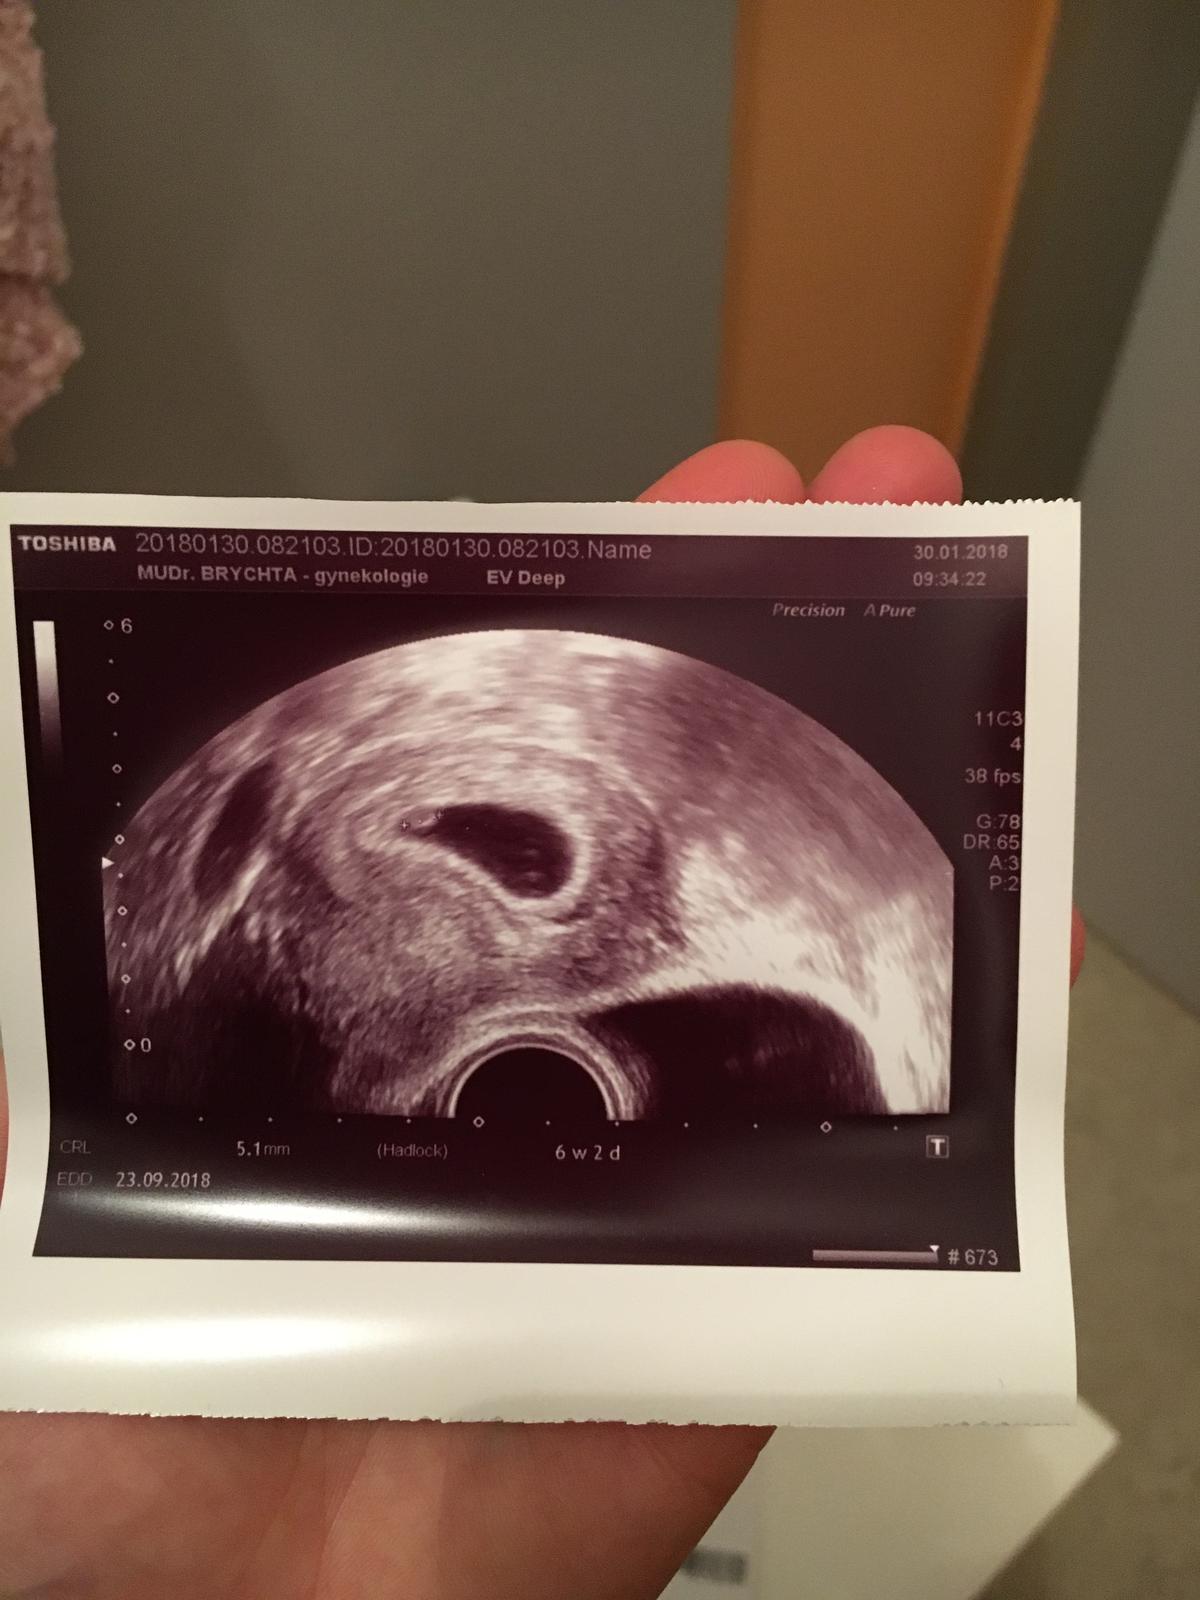

Holky tak já sem dnes byla na prvním vyšetření a mám ofiko potvrzené těhotenství 🤰🏽..v 10tt mě čeká poradna a můj dotaz zní..mám s sebou už vzít taťku?..vím,že to je o měření,vážení,braní krve a dalším ultrazvuku..tak bych ho s sebou chtěla a zapomněla sem se doktora zeptat,zda může přijít se mnou..🙈..přikládám foto,kde vlastně ještě nic není vidět,ale pro mě to znamená strašně moc.😂👌